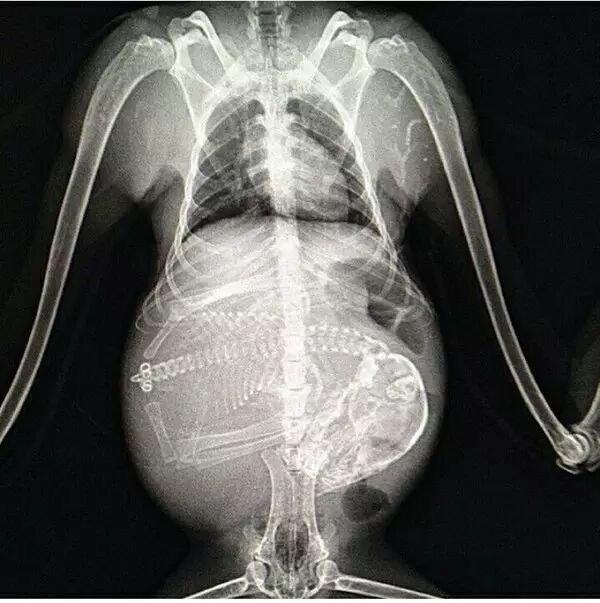

怀孕是一件神圣而又带有神秘色彩的事,她预示着新生命的来临。在动物世界,怀孕是怎样的一种奇迹,以下 14 种动物在怀孕期间的 X 线图片,我们可以通过全新的影像视角探查一番。

• 猴子